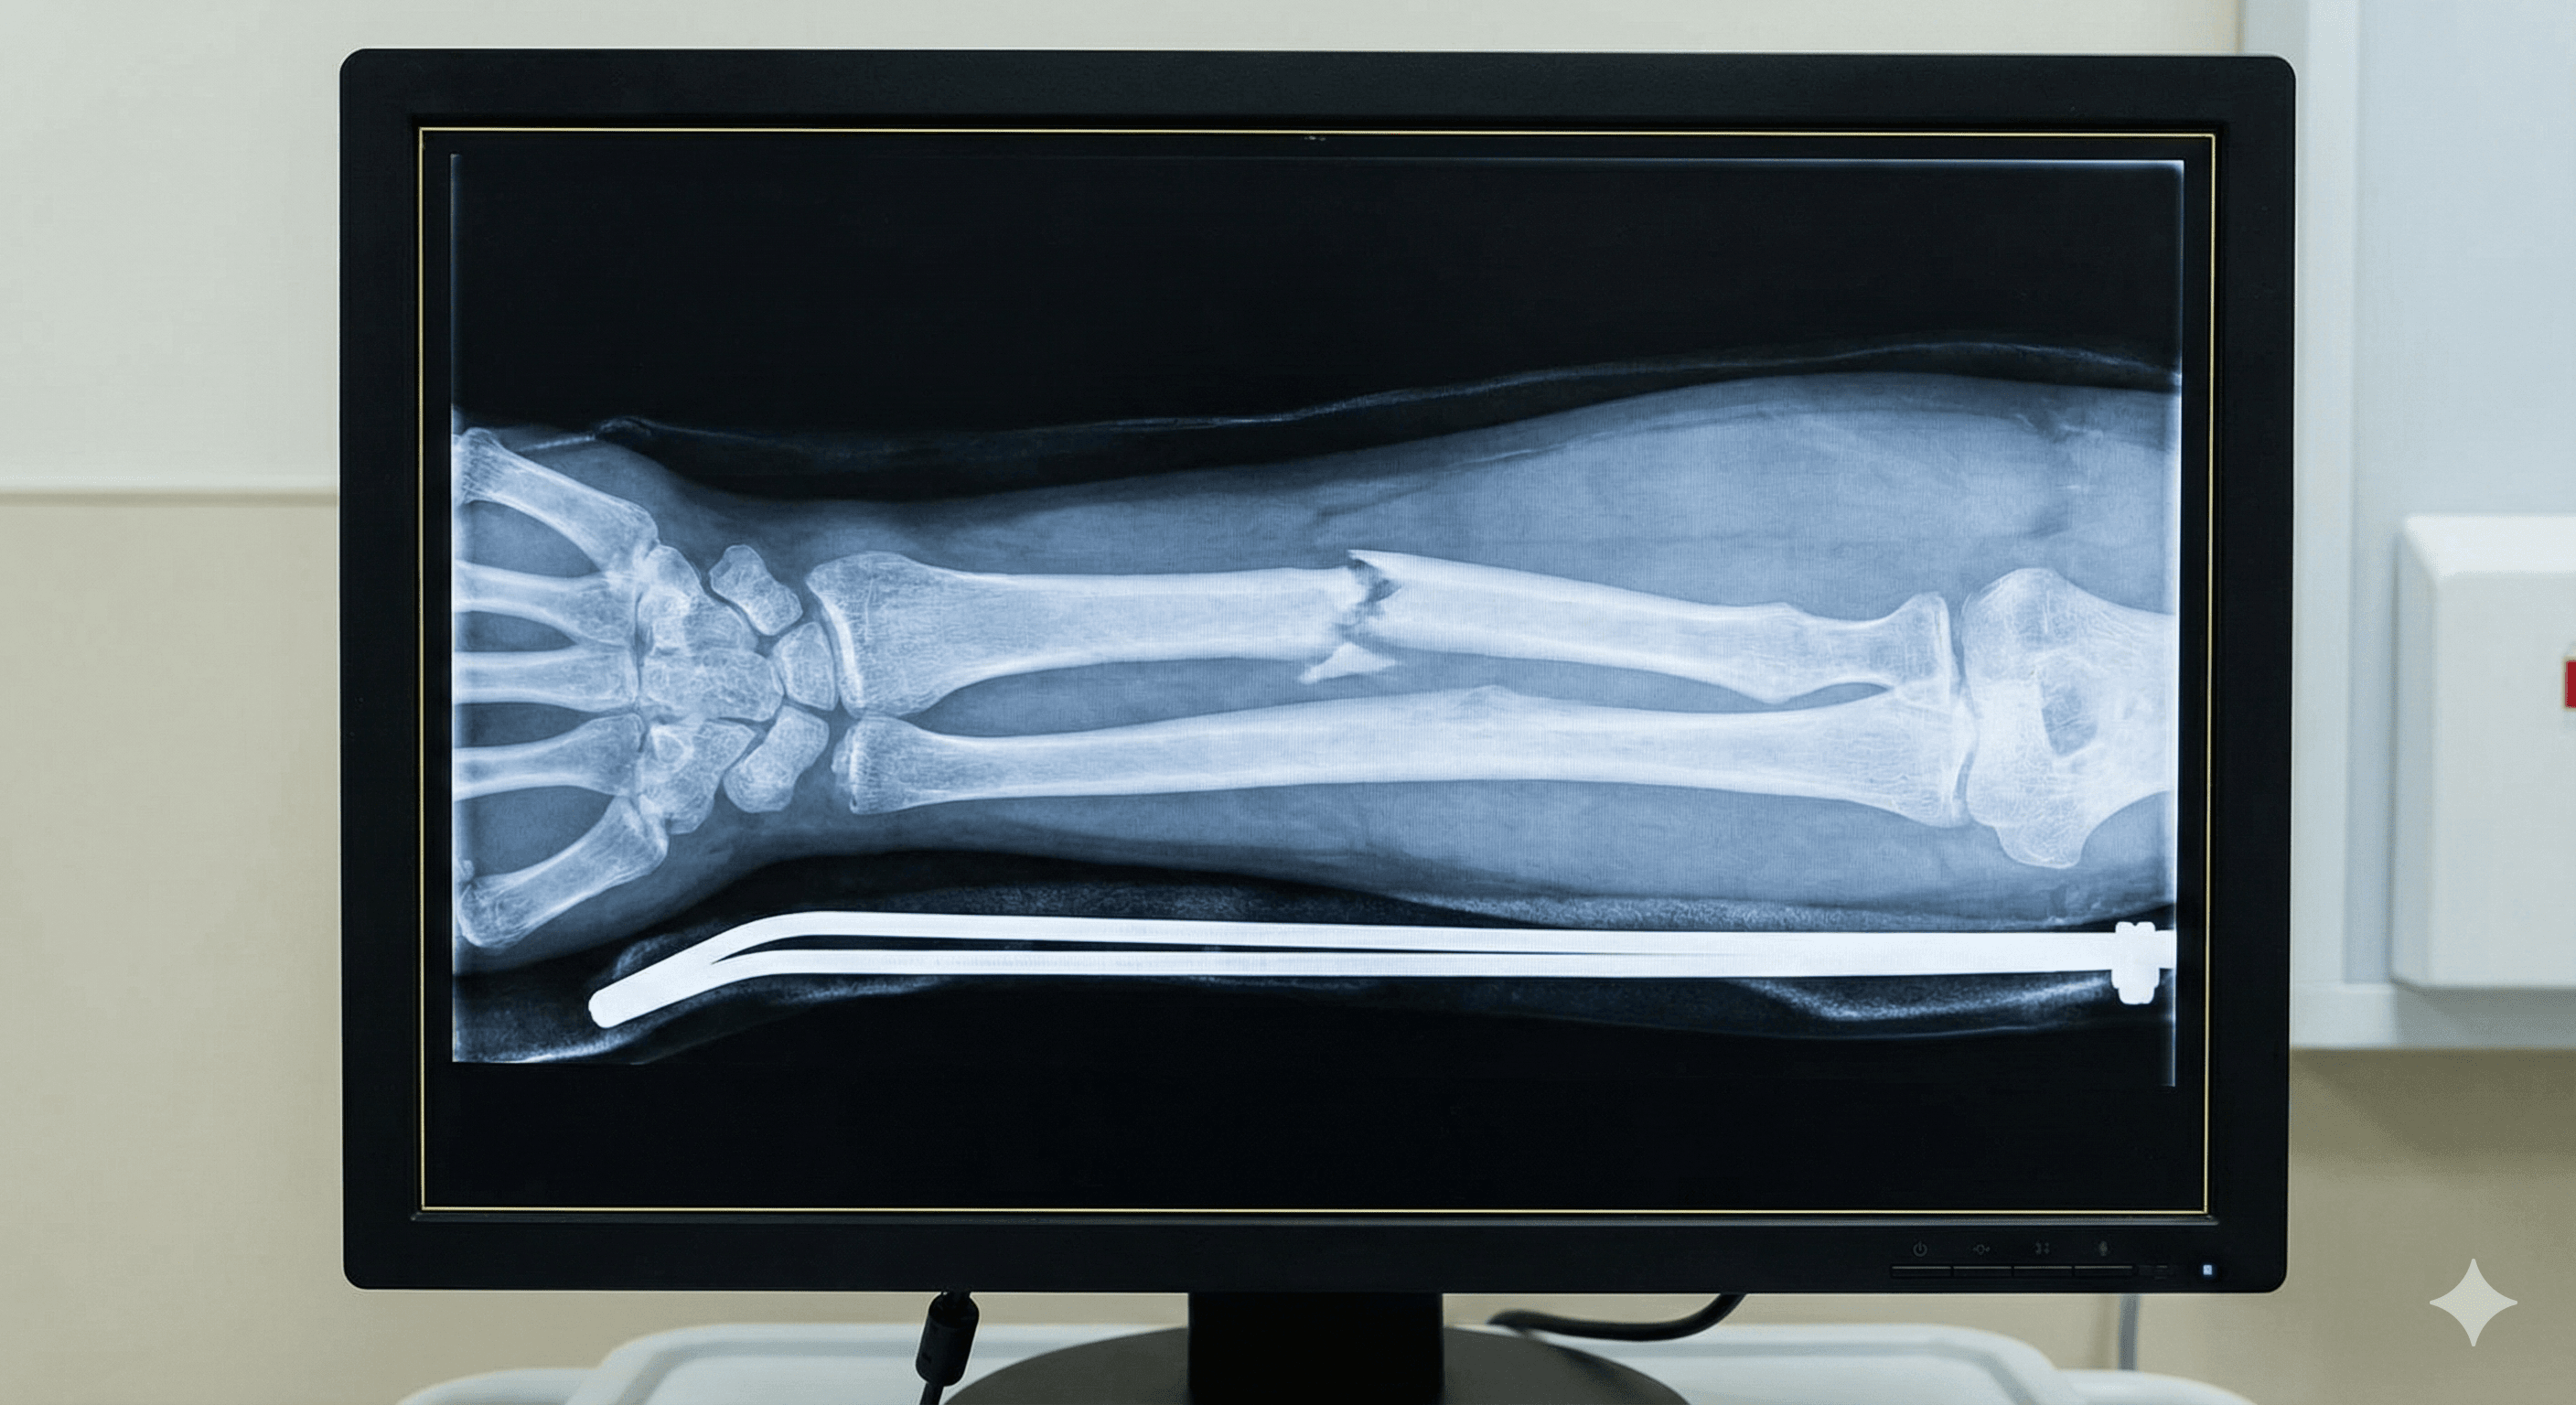

Ruptura parcial o total de un hueso, generalmente causada por traumatismos fuertes, caídas o debilidad ósea.

Manejo integral de huesos rotos, desde inmovilización hasta cirugía compleja.